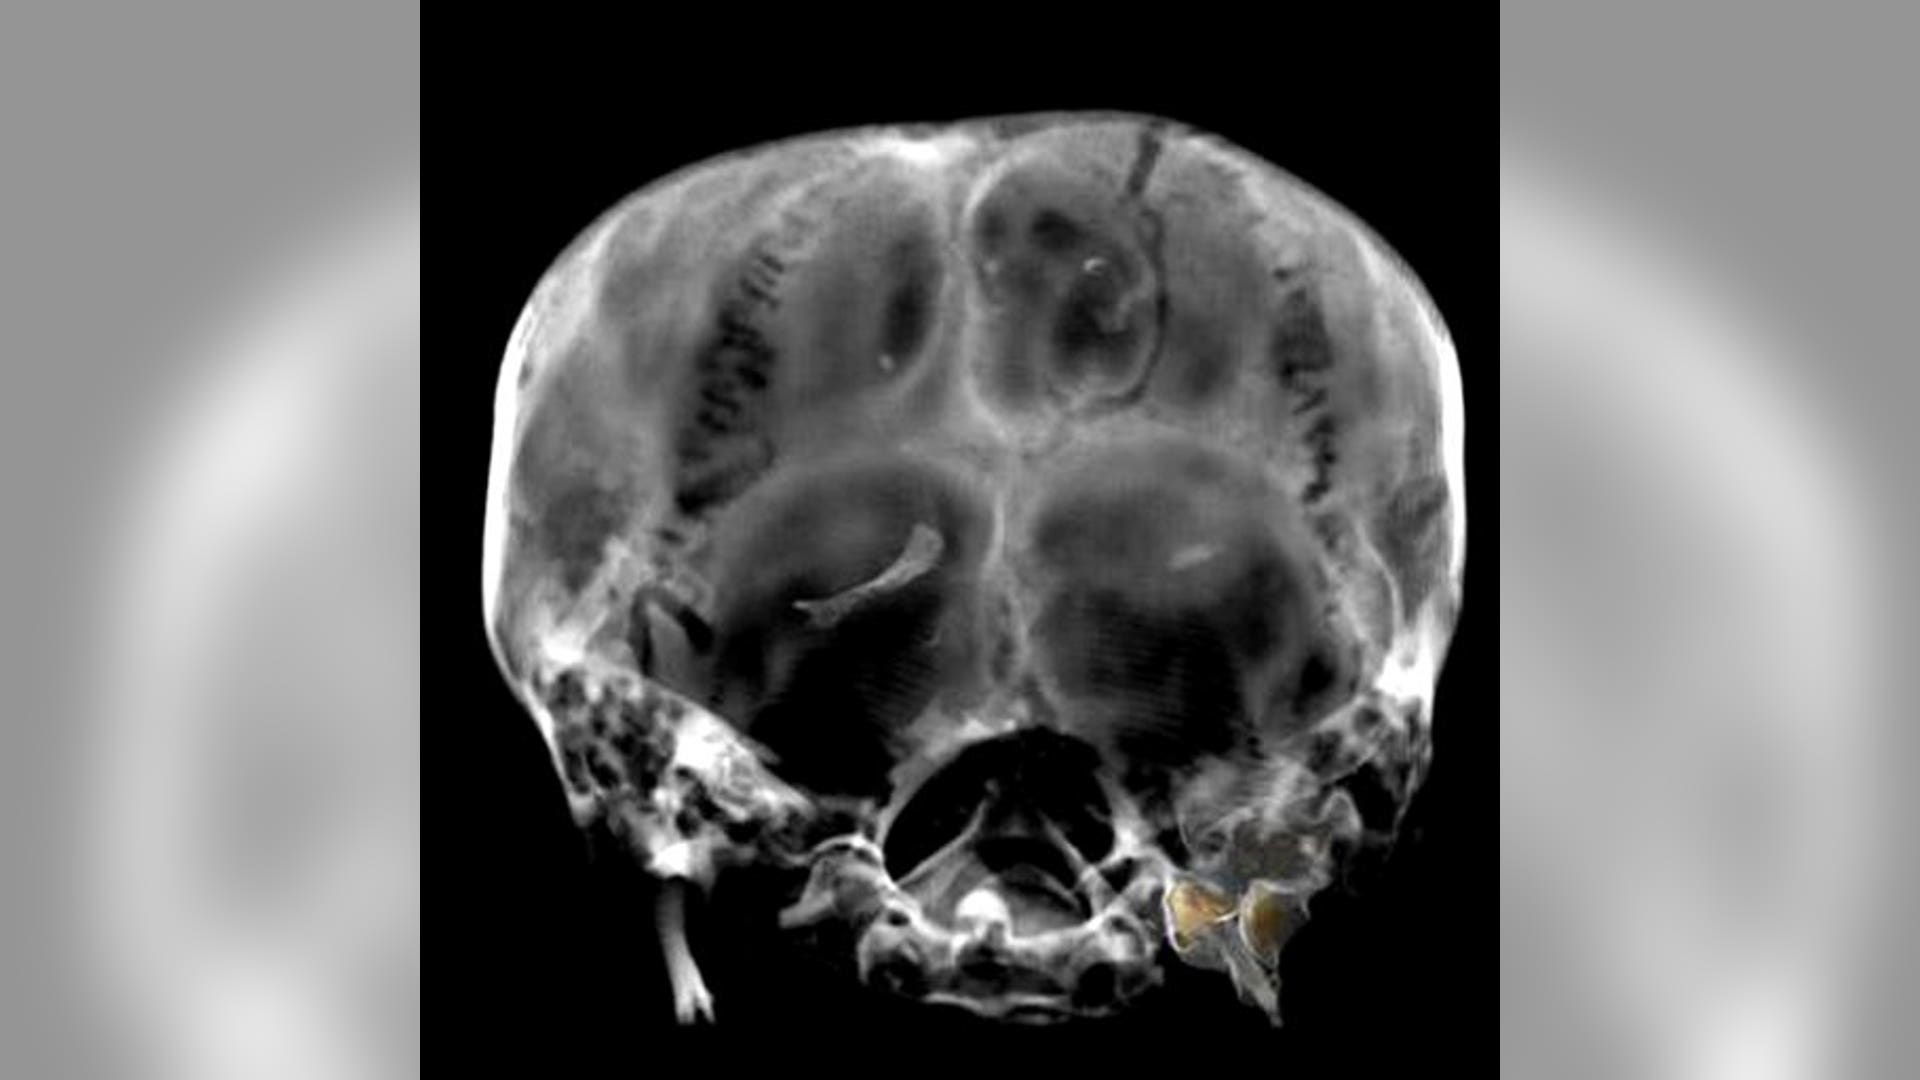

A CT scan of the skull of King Tutankhamun's mummy, in Luxor, Egypt. Egypt's famed King Tutankhamun suffered from a cleft palate and club foot, likely forcing him to walk with a cane, and died from complications from a broken leg exacerbated by malaria, according to the most extensive study ever of his mummy.read moreAP Photo/Supreme Council of AntiquitiesShare

A CT scan from Jan. 5, 2005 of part of the skull of King Tutankhamun's mummy, in Luxor, Egypt. Egypt's famed King Tutankhamun suffered from a cleft palate and club foot, likely forcing him to walk with a cane, and died from complications from a broken leg exacerbated by malaria, according to the most extensive study ever of his mummy.read moreAP Photo/Supreme Council of AntiquitiesShare